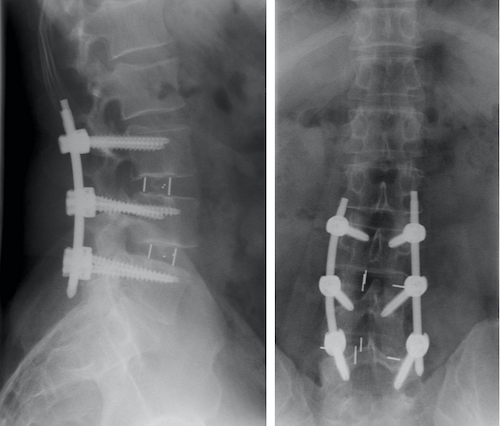

Con una caja aislada no se consigue suficiente estabilidad y se recomienda la colocación de un sistema de sujeción adicional con tornillos (Fig 5) desde la vía lateral o una fijación posterior, pudiendo ser esta percutánea y por tanto menos cruenta (Fig 6).